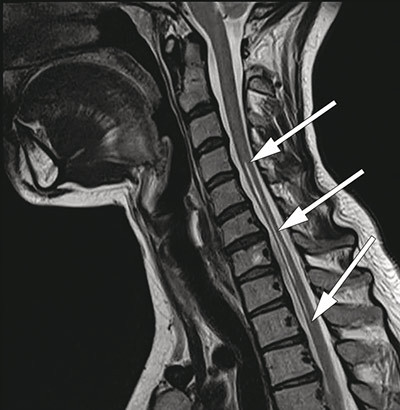

MRI of the spinal cord showed marked atrophy from C4 to Th2 and two longitudinal symmetrical T2-weighted hyperintense lesions from C2 to Th2 (<<<. 3, Fig. 4), confined to the anterior horn area of the medulla. The changes were not considered consistent with syringomyelia, demyelinating plaques, tumour or transverse myelitis. MRI of the head was normal.

Figure 3  Sagittal T2-weighted cervical MRI with atrophy of the medulla from C6 to Th2 and hyperintense lesion from C4 to Th2